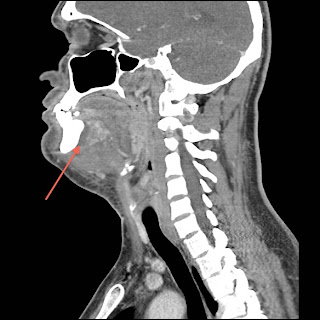

機序としては、通常は下の奥歯の齲歯から舌下・顎下へ感染が広がることで起こります。当症例では膿瘍形成がありましたが、必ずしもあるとは限りません。感染症的な治療としては、嫌気性菌を含めた口腔内常在菌をターゲットにした抗生剤を投与することになります。本症例ではユナシンを投与しました。

呼吸管理的にはこの腫れ上がった舌による上気道閉塞が問題になります。ひどい場合口腔内に収まらないくらいに舌が腫大します。以前にも書きましたが、このような患者さんの気道確保をするときに、次の手を考えずに筋弛緩剤を投与してはいけません。通常の喉頭鏡での挿管で上手くいく可能性はかなり低いです。この場合、声門より上からのアプローチとしては気管支鏡による挿管が適応になります。経験がある方なら盲目的経鼻挿管も良いかも知れませんが、下手につついて上気道閉塞を悪化させることは避けるべきです。声門より下からのアプローチとしては経皮または外科的輪状甲状間膜切開があります。本症例では手術室でまず覚醒した状態のまま外科的輪状甲状間膜切開が行われ、引き続き切開排膿が行われました。

![]() |

| Ludwig's anginaのCT像 矢印は膿瘍部分 |